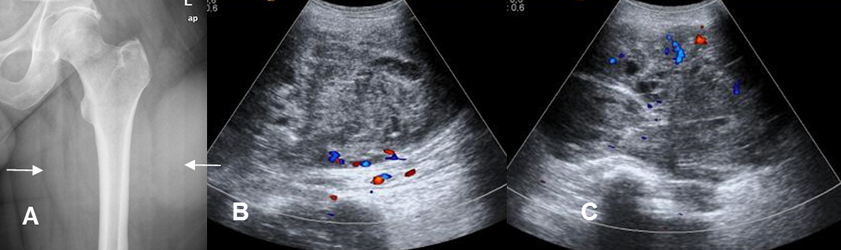

Fig 199. Sarcoma sinovial.

Mayor frecuencia entre 15 y 40 años. Lesión de tejidos blandos, con predominio en la fosa poplítea.

Fig 199 A. Sarcoma sinovial.

A: Rx AP. Prominencia de los tejidos blandos, en la parte interna y externa del muslo.

No se identifica compromiso óseo.

B y C: Ecografía: Se encuentra masa de tejidos blandos de ecogenicidad heterogénea, con algunas zonas quísticas y con aumento focal de su vascularización.